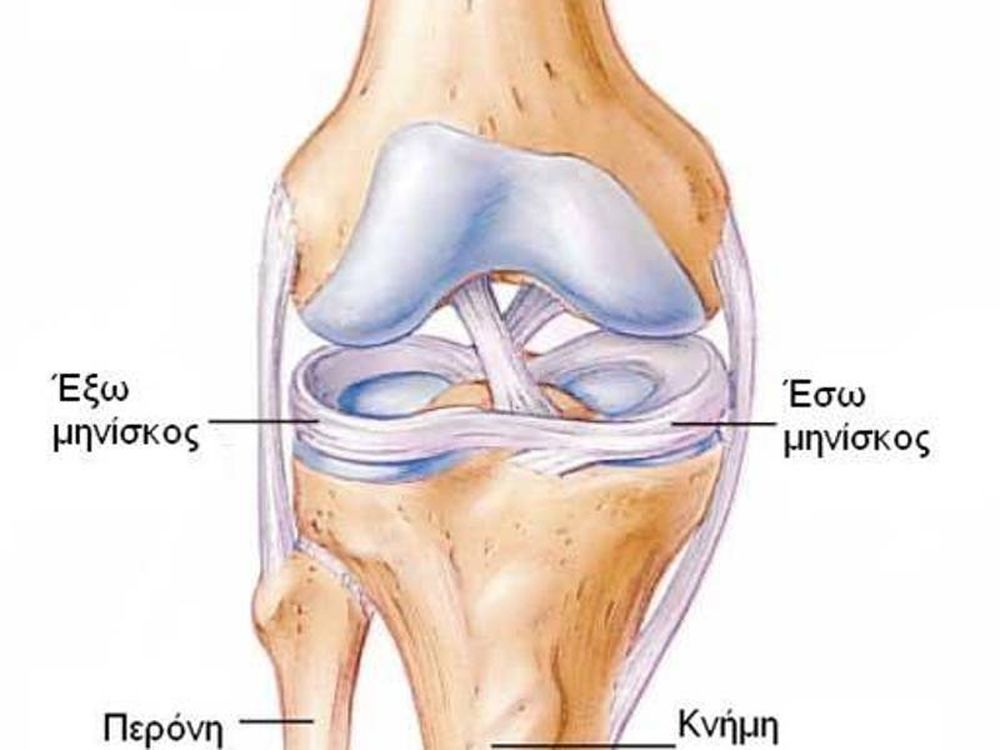

Анатомические изображения менисков и коленного сустава